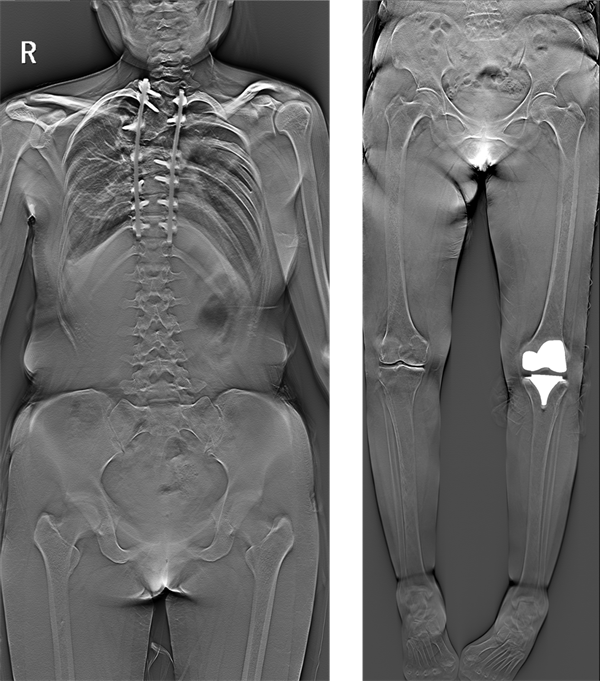

安健科技LF-TOMO一次扫描便能够实现立卧双位下的全脊柱和双下肢的扫描重建,在大部位扫描重建上给患者提供新的低剂量检查手段,可有效抑制金属伪影,查看冠状位影像深层次信息,没有拼接误差。另外,对于双下肢畸形矫正、关节外翻和断骨增高术等手术的术前下肢力线测量和诊断治疗以及术后金属植入物、外固定术的定位显示更加全面、具体,为医生制定更加精准的治疗方案提供了数据支持,应用更加广泛。

(安健科技LF-TOMO1.1米大范围断层融合图像)

对于安健科技LF-TOMO的再度创新,不仅在技术上,实现了1.1米超大范围扫描,使一次曝光扫描就能得到全脊柱和双下肢断层融合重建图像,让检查更简单便捷;更增添了负重位的扫描体位,在各种病灶的检查上,为医生在病灶的检出和治疗上提供了一种新的方法和选择。